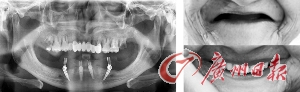

原广东省口腔医院副院长薛国初教授说,在进行种植牙前,首先采用计算机精密设备进行口腔内检测,呈现受术者口腔三维CT曲面数据,精确测量出传统X光片所无法测量出的牙槽骨的质和量,牙骨高度、宽度、张口度、咬合状况、耐受度等数十项数据,在3D种植导板的指引下种植,避开重要的神经和血管,种植牙便可以安全及长效。

具体来说,两颗前牙部位的种植体采用垂直植入牙槽骨内,两颗中远部位的种植体采取倾斜角度植入,四颗种植牙根由此形成“W”状,获得最大的骨接触面积,撑起的“拱形搭桥”连接牙冠,使受力会均匀地分布到整体。节省费用不说,还大大减低了创伤面!